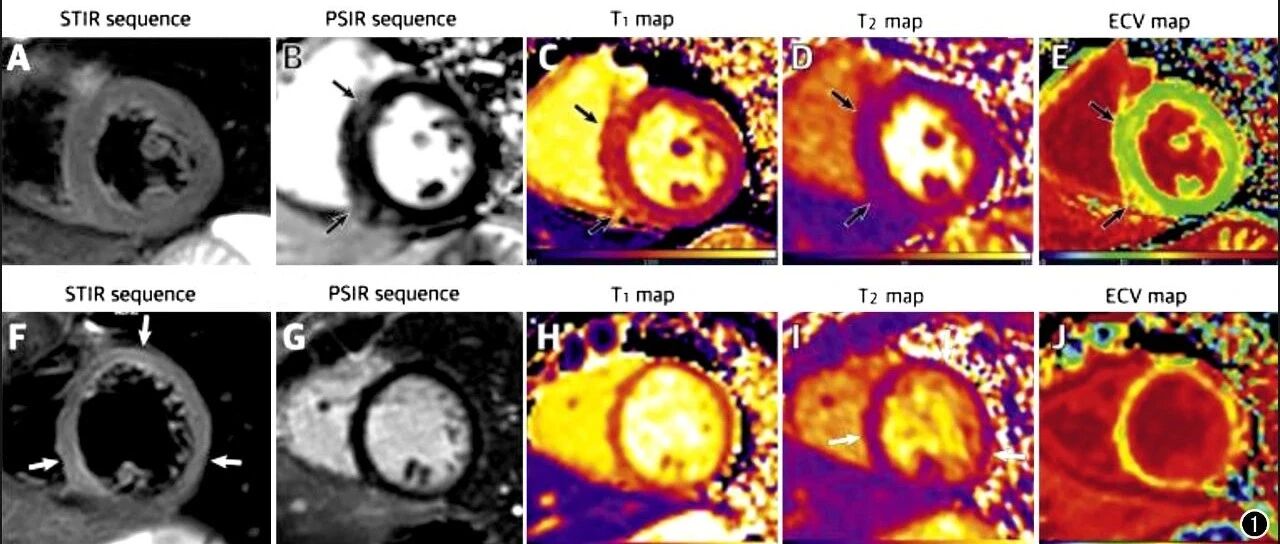

心脏MRI评估COVID-19心脏受累研究进展 放射学实践 · 公众号 · 医学 · 8 月前 · |